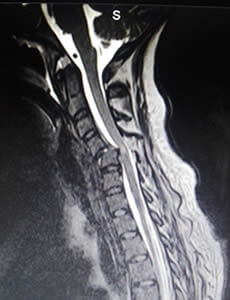

Dolor de Cuello